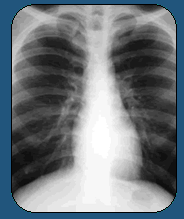

When put side by side, his CAT scans from before and

after treatment are hard to believe. The dark hole

is gone, and only a small white scar tattoos his lung.